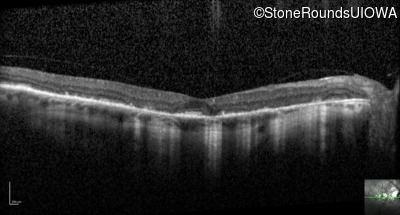

Optical Coherence Tomography - Left - 20/20 -1

Exemplar / OCT Stack